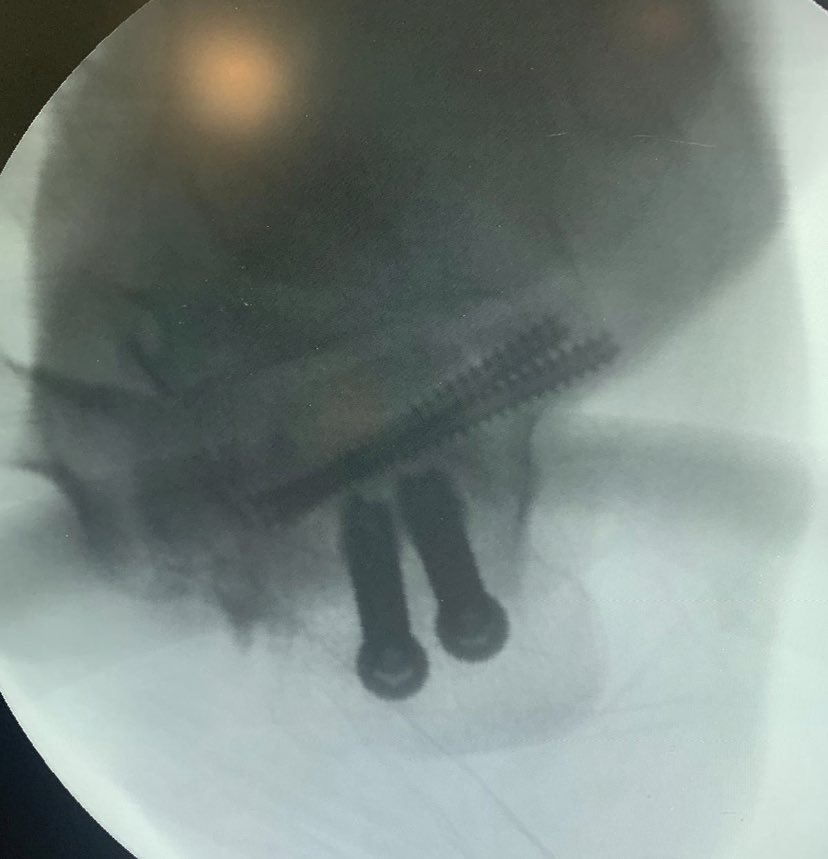

6-year-old child, post FD with Lt elbow swelling and pain.

What’s your further management? @Davembmd @DrBhavinJadav @Plexusorthoexam @Pranai_B @traumaticum @MatthewHarbMD @CPOrthopedics @pratikorho @ChrisGeeOrtho @itius @MGalanOlleros